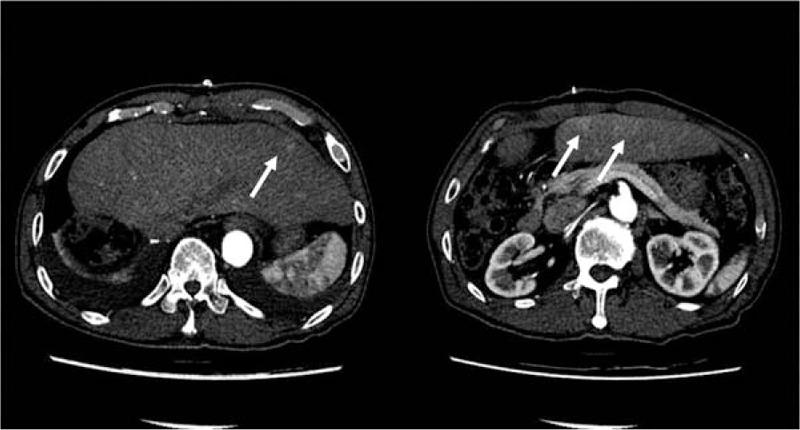

Metastatic hepatocellular carcinoma (HCC) of the right ventricle is very rare and difficult to diagnosis.A 79-year-old man who underwent right hemi-hepatectomy for HCC was admitted to our hospital for chest pain, severe dyspnea, and orthopnea. The echocardiogram showed a tumor located in the right ventricle. A biopsy was obtained, and histopathological findings confirmed metastatic HCC. Palliative resection of the tumor was performed.There is no standard treatment for metastatic HCC into the right ventricle. Thus, treatment should be individualized to the patient, and a multidisciplinary approach should be used.

右心室转移性肝细胞癌(HCC)非常罕见且诊断困难。一名因HCC接受右半肝切除术的79岁男性因胸痛、严重呼吸困难和端坐呼吸入住我院。超声心动图显示右心室内有一个肿瘤。进行了活检,组织病理学检查结果证实为转移性HCC。对肿瘤进行了姑息性切除。对于转移至右心室的HCC尚无标准治疗方法。因此,治疗应根据患者个体情况而定,并采用多学科方法。